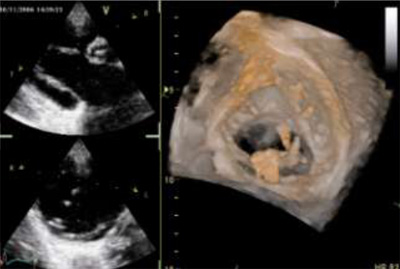

感染性心内膜炎による三尖弁の疣贅

感染性心内膜炎による三尖弁(さんせんべん)の疣贅(ゆうぜい)